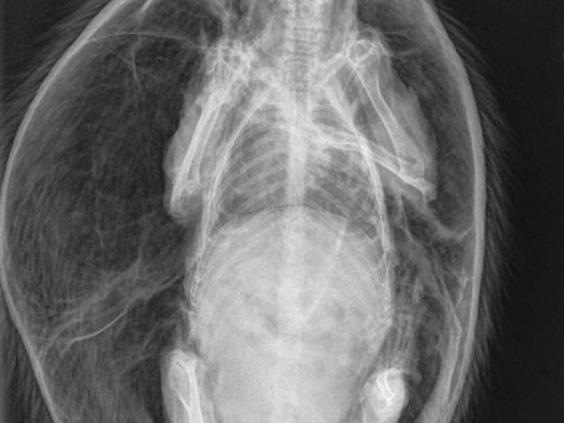

X-ray shows skin inflated to twice normal size (RSPCA)

“I took the stricken animal straight to Peak Vets in Sheffield, where he was X-rayed and they released some of the air from under his skin.

“This poor chap was almost twice its natural size, literally blown up like a beach ball with incredibly taut skin.